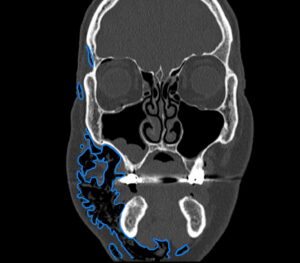

Dental Free Air CT Coronal Annotated. JETem 2025